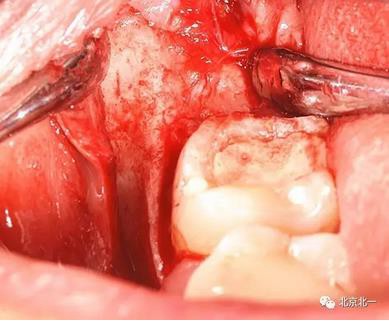

圖六:切開翻瓣, 看見骨面清晰,未見智齒

圖十:實(shí)際情況:看到么在第二磨牙頰側(cè)接近近中區(qū)域。關(guān)鍵牙顏色和骨顏色一致, 只有牙冠部分是白色能看出來, 但是它卻深深的把頭埋下。